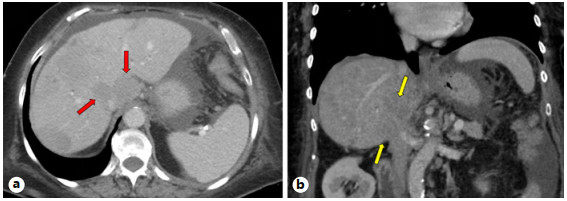

Abstract: Small bowel-origin carcinoid tumor is indolent but may metastasize relentlessly to various sites, including the liver. Over the past 9 years, we have treated a 69-year-old woman who has undergone 5 percutaneous liver ablations, 5 hepatic intra-arterial chemoembolizations, an ovarian cryoablation, and a trans-ventral hernia mesenteric cryoablation. These interventions are all related to her inoperable carcinoid malignancy. After the patient presented with swelling of the abdomen and both lower extremities, computed tomography (CT) angiography was performed, revealing a circumferential hepatic metastatic mass encasing the intrahepatic inferior vena cava (IVC) and extensive third spacing of fluids specific to the IVC distribution below the diaphragm. A venogram of the intrahepatic IVC revealed extrinsic compression causing 95% narrowing of the vessel. A balloon was advanced to the level of the lesion and inflated, increasing the caliber of the vessel. Subsequently, 2 covered aortic stent graft cuffs were deployed in an overlapping fashion within the lumen of the IVC, traversing the area of narrowing. Next, an open-cell aortic dissection stent was placed across both overlapping aortic stents from the renal veins to the hepatic veins. Following this, three 17-gauge cryoablation probes were inserted into the segment 1 intrahepatic lesions encasing the newly stented IVC via an anterior percutaneous approach. Two 10-min freeze cycles were performed with intraoperative CT imaging, demonstrating circumferential coverage of the lesions. Posttreatment venogram revealed patent stent grafts within the intrahepatic IVC, and restoration of vessel patency. No immediate postoperative complications were noted. The patient’s abdominal and lower extremity swelling resolved completely within 1 week after procedure. Two-month follow-up CT demonstrated markedly decreased size of the metastatic lesions and no adverse effects. Six- and 9-month PET-CT scans demonstrated maintained patency of the IVC stent. This palliative procedure allowed the patient to maintain good performance status and alleviated her symptoms of IVC syndrome. The radial force generated by the multiple aortic stents will ostensibly maintain the patency of the intrahepatic IVC. Cryoablation of the encasing metastatic lesion was performed with markedly decreased size of the tumor on the 2-month follow-up.